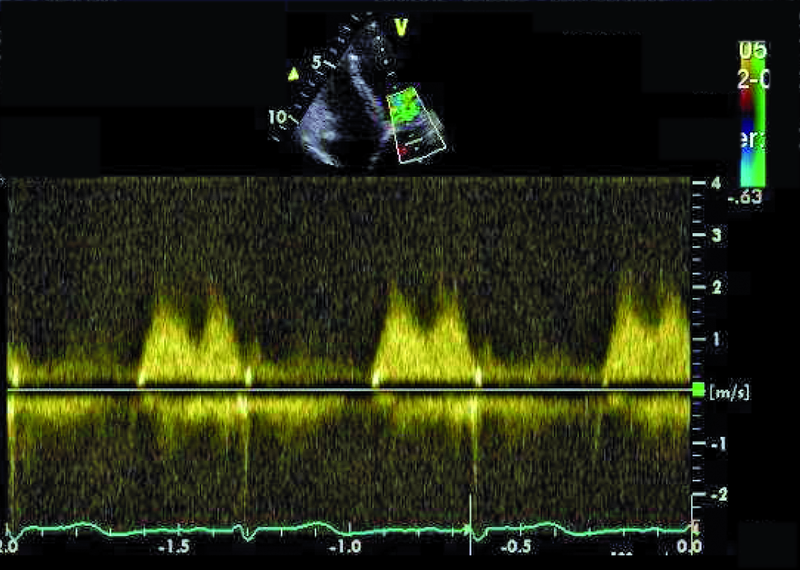

Przedstawiona chora, prawie dorosła kobieta, znajduje się w tej drugiej grupie. Jamy serca są u niej niepowiększone, a mięsień ma prawidłową grubość (ryc. 1). Rozpoznanie membrany w jamie lewego przedsionka z prawidłowym obrazem zastawki mitralnej nie nastręcza trudności. Membranę można dostrzec w wielu projekcjach (ryc. 2-4). Badanie przezprzełykowe pozwala na bardziej precyzyjne określenie średnicy otworu, która zazwyczaj waha się od kilku milimetrów do centymetra. W omawianym przypadku otwór jest duży i na podstawie samej jego wielkości można przypuszczać, że nie powoduje obstrukcji przepływu (membrana w projekcji na rycinie 4 znajduje się powyżej zastawki). Tryb doplera ciągłego (ryc. 5) także nie potwierdza zaburzeń przepływu i trudno się spodziewać, by w takiej sytuacji mogło dojść do podwyższenia ciśnienia w żyłach płucnych, włośniczkach i pniu płucnym. Średnica pnia płucnego (21 mm, ryc. 6) jest dowodem na panujące w nim niskie ciśnienie (nie zarejestrowano w badaniu fali zwrotnej trójdzielnej). Serce trójprzedsionkowe z niskim gradientem śródprzedsionkowym przy braku dodatkowych nieprawidłowości (np. przecieku międzyprzedsionkowego lewo-prawego bądź prawo-lewego – zależnie, z jaką jamą ubytek się komunikuje) nie wymaga leczenia operacyjnego. Pacjentka wymaga dalszej kontroli, ponieważ po wielu latach choroby mogą pojawić się napadowe lub utrwalone nadkomorowe zaburzenia rytmu serca, będące wyrazem zmiany geometrii przedsionka.